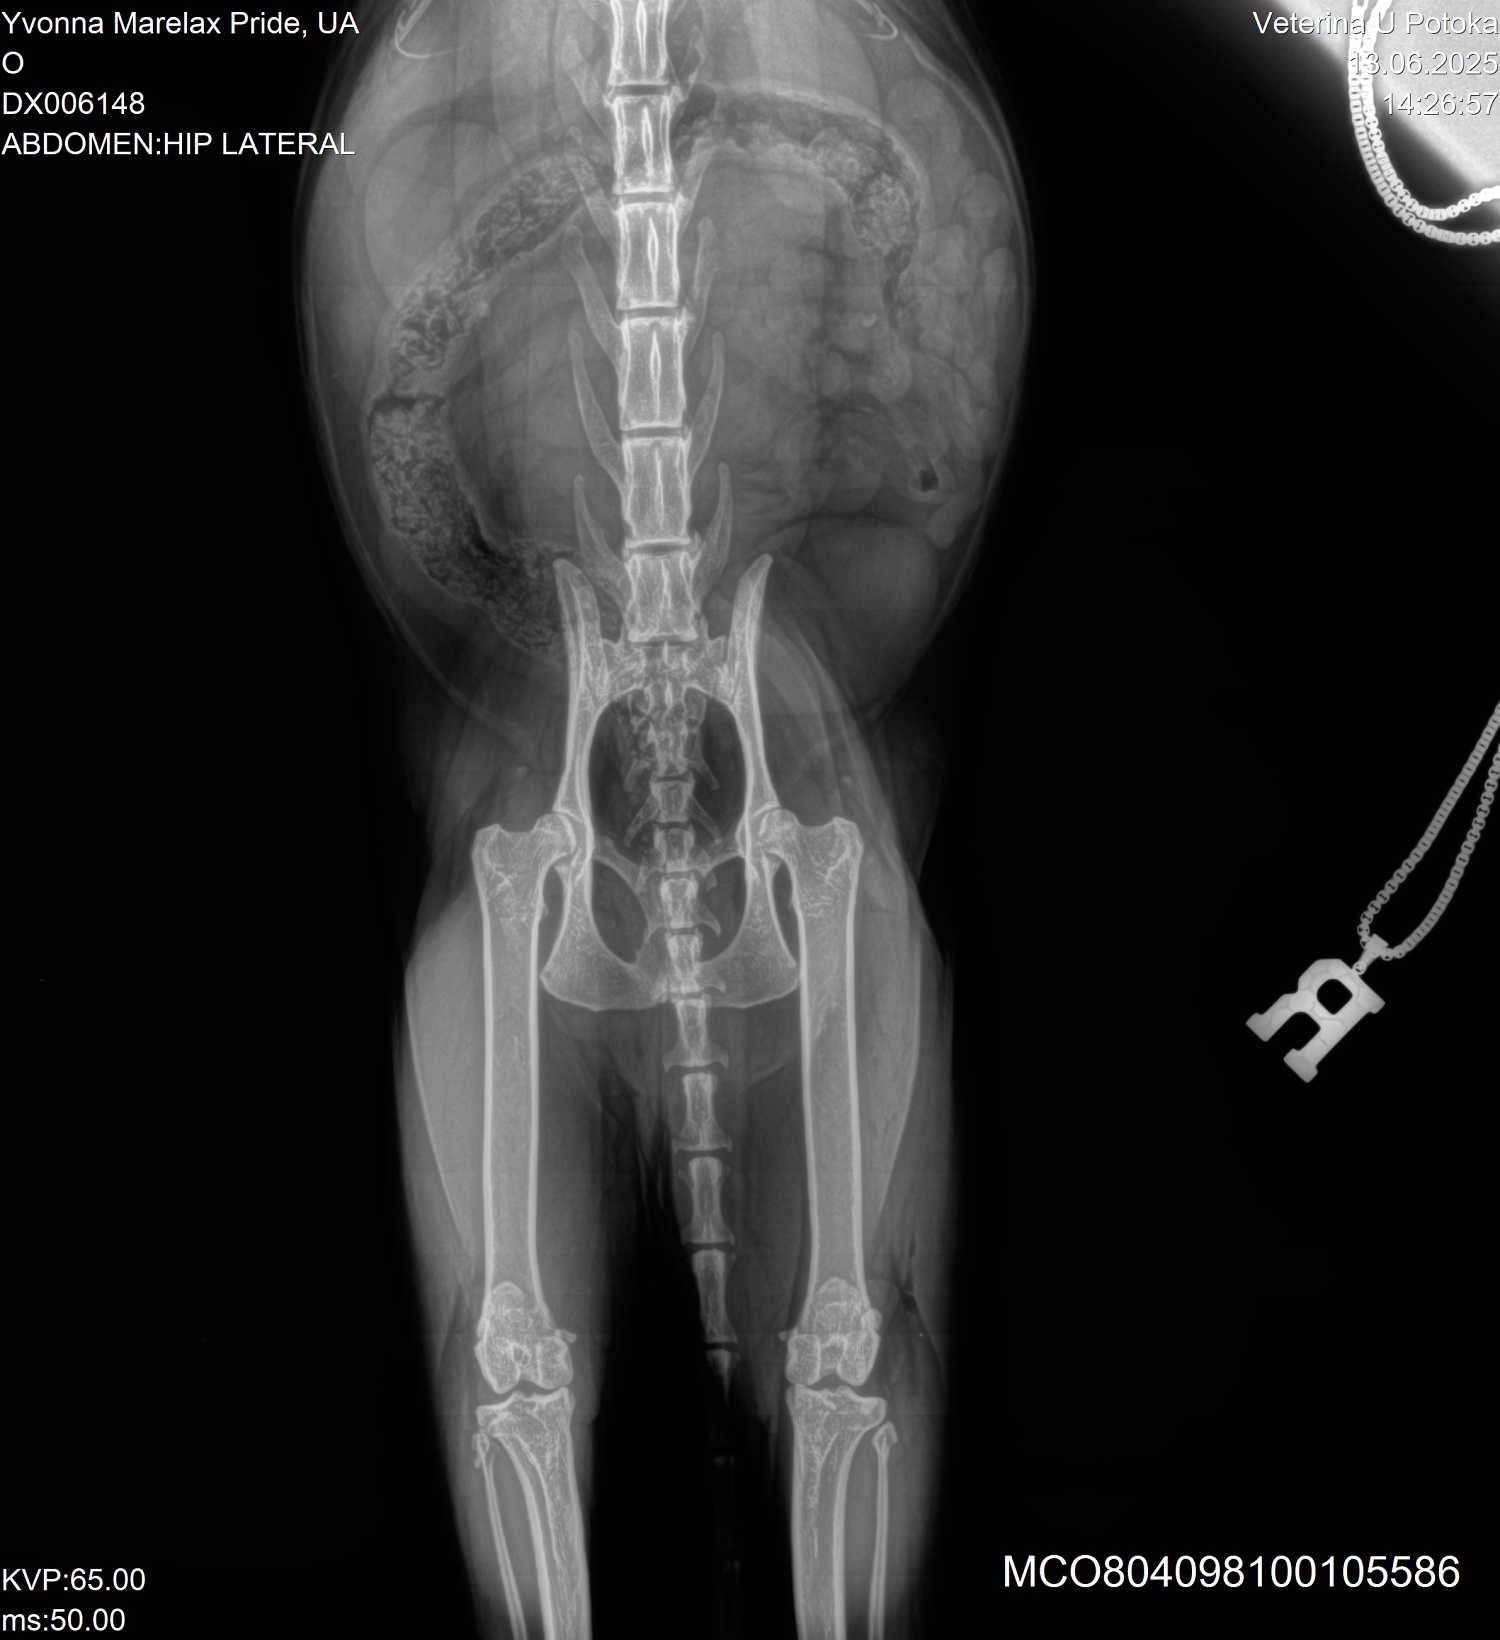

HD: 24.02.2021; 08.11.2023